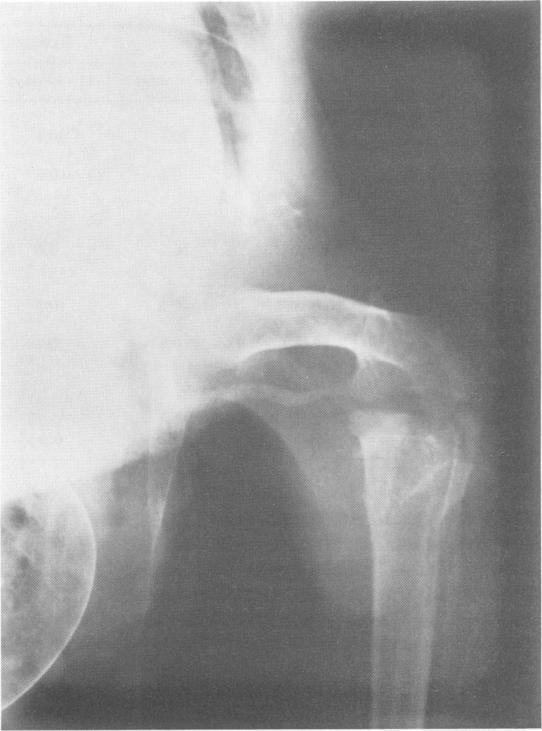

Experiments were performed on obligatory bipeds to study the effects of an arteriovenous fistula on a devascularized ischemic limb. Retrograde flow of arterial blood entering the venous system by way of an arteriovenous fistula was demonstrated. Venous valves appeared not to interfere with retrograde arterial flow. The data from these experiments indicate that a "Y" type arteriovenous fistula can lead to functional revascularization in the ischemic limb with arterial obstruction. The dual mechanism of retrograde arterial flow in venous channels and the stimulation of collateral flow adjacent to the fistula seemed to be critical factors. Since a peripheral arteriovenous fistula is a potent stimulus to arterial collateralization in the extremity, its application is worthy of consideration in certain selected patients with advanced and otherwise inoperable arterial occlusive disease.